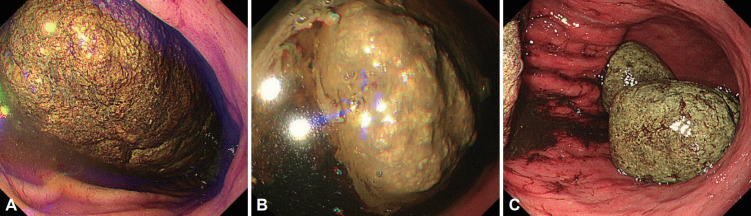

Bezoars, including phytobezoars, trichobezoars, and pharmacobezoars, are accumulations of undigested substances in the gastrointestinal tract. We report three cases of gastric bezoars. Case 1: An 86-year-old woman presented with a one-month history of abdominal pain and vomiting. Esophagogastroduodenoscopy revealed gastric bezoars; consumption of 2 L of cola daily for 2 weeks resulted in complete disappearance of the bezoars. Case 2: An asymptomatic 63-year-old woman underwent esophagogastroduodenoscopy, which revealed a gastric bezoar. Cola spraying and endoscopic lithotomy were ineffective; therefore, the patient underwent laparoscopic removal of the bezoar for management of small bowel obstruction secondary to the bezoar fragments. Case 3: A 6-year-old girl with a history of pica underwent two laparoscopic surgeries 10 months apart for recurrent trichobezoars. We report our treatment approach in three patients who presented with gastric bezoars.